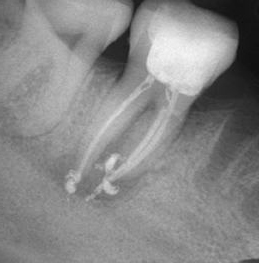

Запълване с препресване

Ендодонтия